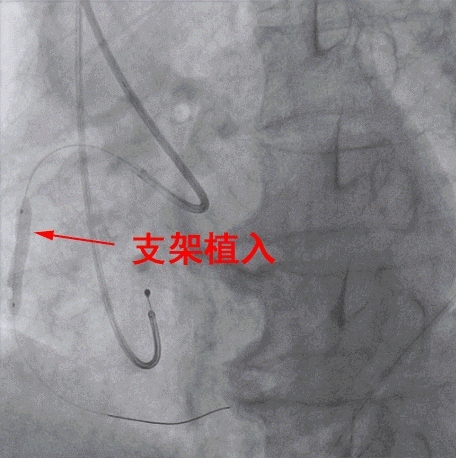

專家們在DSA引導下,經右手桡動脈穿刺,置入導絲将擴球囊送至右冠脈,對閉塞處進行擴張,緊接着放置一枚支架至病變處,再用後擴球囊對支架進行擴張、塑形。DSA顯示支架貼壁良好,原先閉塞的右冠狀動脈已完全暢通,血液迅速恢複灌注,心肌重新獲得血液供養。術後患者心率維持70次/分,各項生命體征平穩,成功脫離死神。